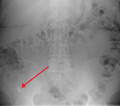

X-ray showing fecalith which has caused appendicitis.jpg

A fecalith marked by the arrow which has resulted in acute appendicitis.